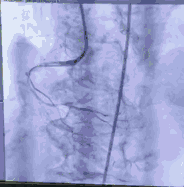

采用右股动脉为主入路,左股动脉为冠脉保护预留。先尝试干预PL慢性闭塞病变,XT-R导丝通过闭塞病变,在球囊锚定下,1.25球囊通过病变扩张。复查造影显示闭塞远端血管细小,放弃进一步干预右冠。

顺利跨瓣,测得跨瓣压差62mmHg。送20mm球囊扩张主动脉瓣,经右桡动脉猪尾导管造影,冠脉切线位未见右冠脉显影。为策安全,决定对RCA行冠脉保护,送JR4导管及guidzila和3.5球囊行冠脉保护。置入24mm微创 vitaflow瓣膜标准位释放。复查造影显示少量主动脉瓣返流,左右冠显示良好,撤除右冠保护。术后测压差为10mmHg。缝合双侧股动脉。术后恢复良好,次日转回普通病房,顺利出院。